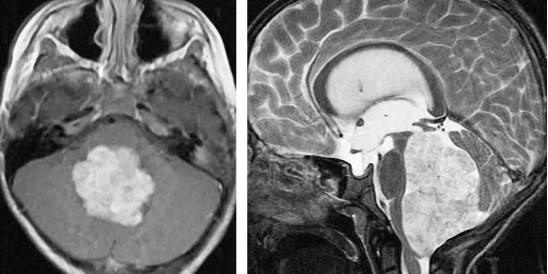

图3. 图示为向四脑室延伸和压迫的蚓部毛细胞星形细胞胶质瘤。肿瘤呈囊性,伴有明显强化的结节。囊壁未见强化,无需手术切除。